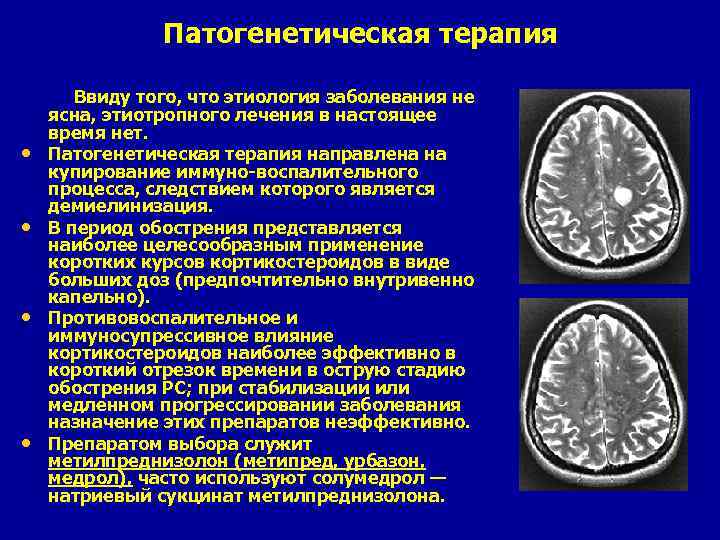

Патогенетическая терапия Ввиду того, что этиология заболевания не • • ясна, этиотропного лечения в настоящее время нет. Патогенетическая терапия направлена на купирование иммуно-воспалительного процесса, следствием которого является демиелинизация. В период обострения представляется наиболее целесообразным применение коротких курсов кортикостероидов в виде больших доз (предпочтительно внутривенно капельно). Противовоспалительное и иммуносупрессивное влияние кортикостероидов наиболее эффективно в короткий отрезок времени в острую стадию обострения PC; при стабилизации или медленном прогрессировании заболевания назначение этих препаратов неэффективно. Препаратом выбора служит метилпреднизолон (метипред, урбазон, медрол), часто используют солумедрол — натриевый сукцинат метилпреднизолона.